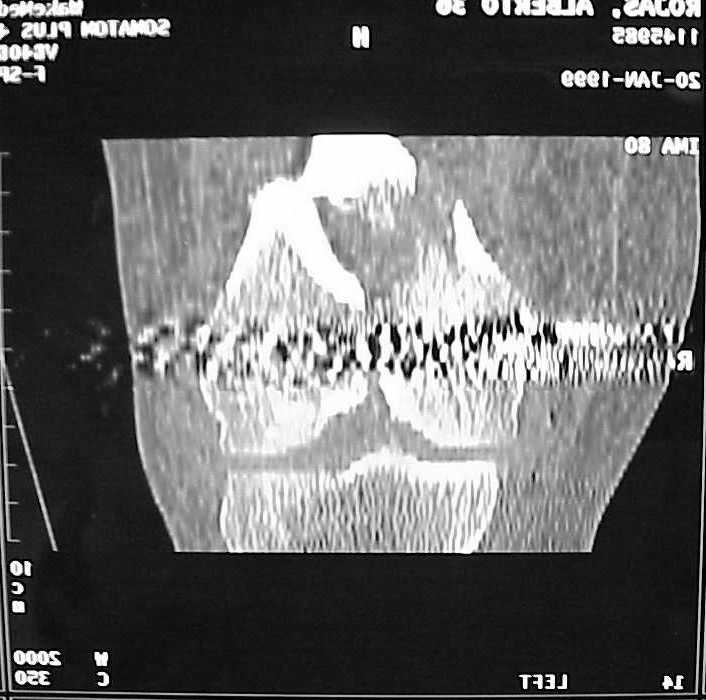

place one anterior to where IMN will go if anterior cortex if insufficient and AP screws on either side of the IMN out of the trochlea to provide some additional varus/valgus stability. I worry about the leg going into valgus w/the lack of lateral cortex.

See attached case that was done several years ago before LISS. He had comminuted trochlea and anterior blocking screws were used to prevent anterior IMN cut-out.